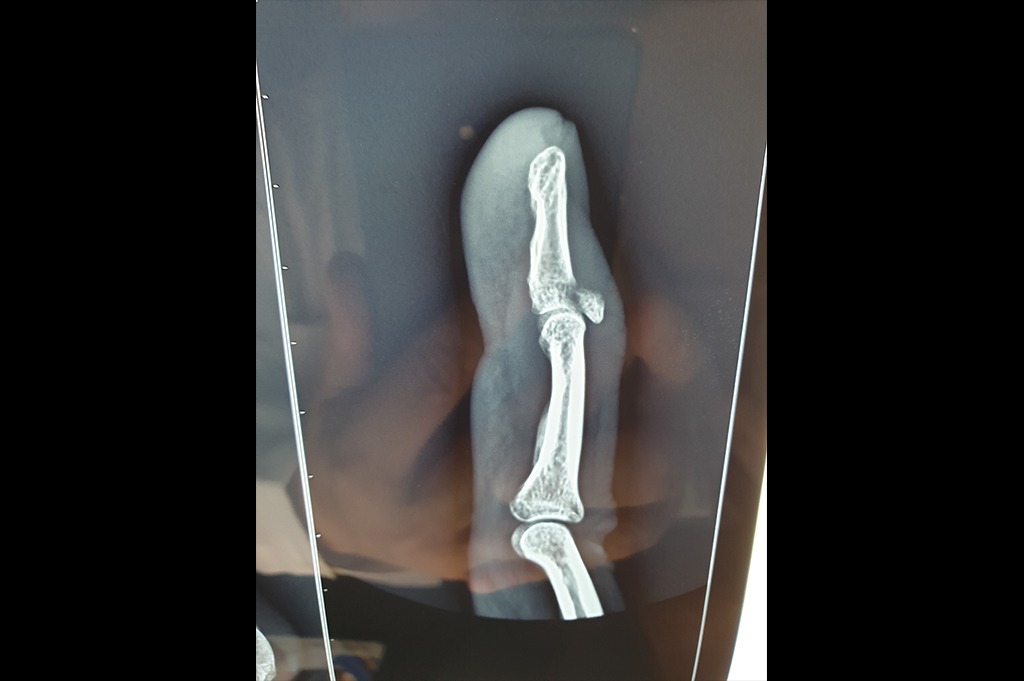

Finger Tip Injury - JESS